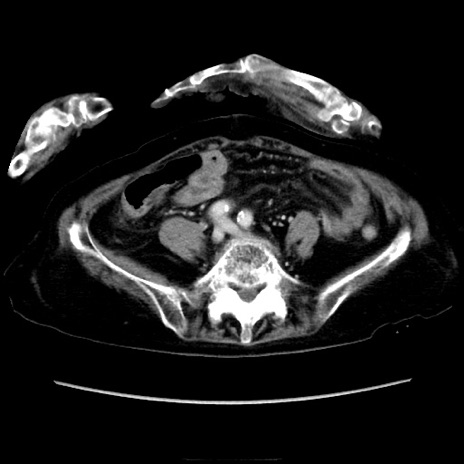

症例40(横断像)

【症例】90歳代女性

【主訴】腹痛・嘔吐

【現病歴】 食欲低下、嘔吐があり昨日他院受診。肺炎と診断され入院となる。入院後より腹部全体に圧痛あり。胃管留置され経過みていたが、症状持続するため、

当院転院となる。

【既往歴】胸椎圧迫骨折、胆石症

【身体所見】腹部:中央に激痛あり、圧痛あり、反跳痛不明

【データ】WBC 17100、CRP 18.82

横断像